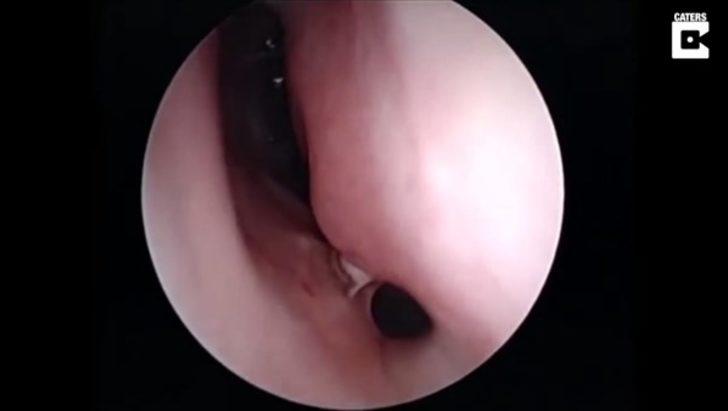

Burnunda garip bir hareketlilik hisseden hasta doktora göründü.

Doktor ise ufak bir operasyon yaptı.

Yüzerken burnuna kaçan şey doktorları bile şaşırttı